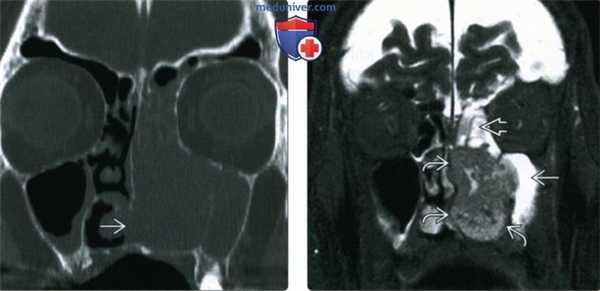

(Слева) При корональной КТ (реконструкция) визуализируется большое объемное образование, заполняющее полость носа слева, с эрозией ипсилатеральных носовых раковин. ПКР приводит к эрозии нижних отделов носовой перегородки. Края образования сложно определить.

(Справа) При корональной MPT STIR определяются края опухоли с гипоинтенсивным сигналом. «Запертый» секрет в верхнечелюстной и решетчатой пазухах гиперинтенсивен по сравнению с опухолью. Гипоинтенсивный сигнал (Т2) может быть обусловлен высоким Я:Ц соотношением.